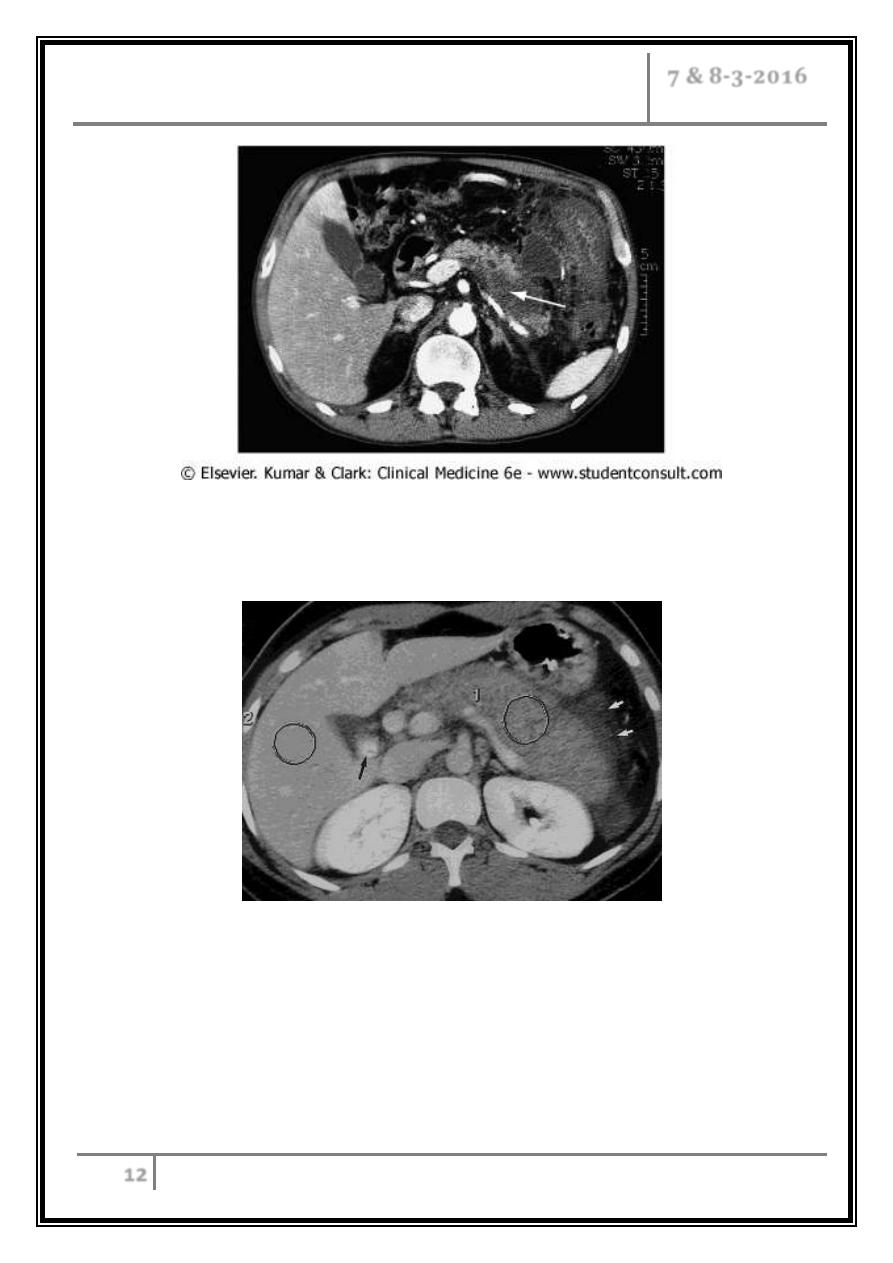

CT scan in patient with acute pancreatitis showing necrosis of the

pancreatic parenchyma (arrow) and a fluid collection extending outside the

gland with inflammatory thickening of the colon.

Gallstone-induced pancreatitis in 27 year-old woman

Transverse CT scan obtained with intravenous and oral contrast material

reveals a large, edematous, homogeneously attenuating (73-HU) pancreas (1)

and peripancreatic inflammatory changes (white arrows). Although the

attenuation values are low, there is no pancreatic necrosis. Calcified gallstones

are seen in gallbladder (black arrow). 2 = liver (140 HU).